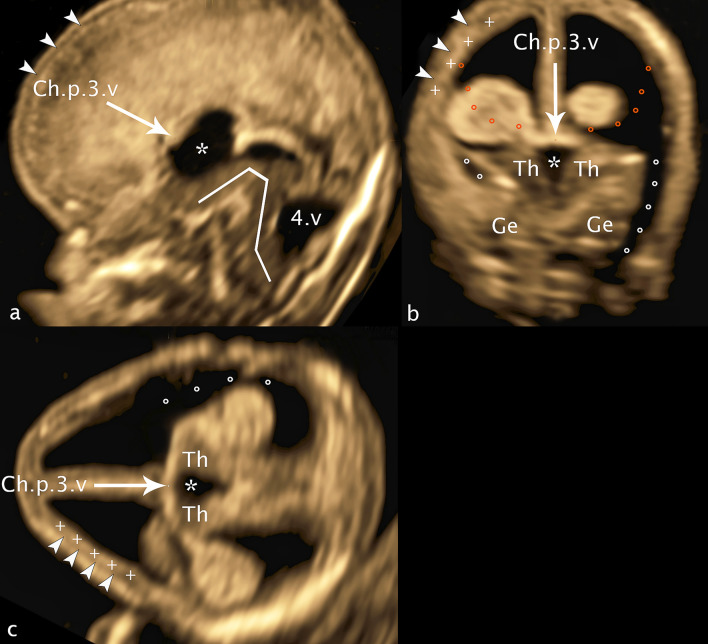

In the axial plane (Fig. 3a, c, d) with marker dot analogous in choroid plexus 3.v between the foramina of Monro, the plane located just above the hemispheric peduncle, the developing neocortical wall, hypoechoic and narrow presents at the very outside in the concave curvature of the developing insula. Medially adjacent, the basal ganglia can be visualized laterally as a concave, medially as a convex structure cap-shaped again as demonstrated in the coronal plane. Analogous in this section the merging of GE into the cerebral mantle can be demonstrated frontally and temporally, the fibers of capsula interna dividing the basal ganglia into caudate and putamen (nucleus lentiformis). After the section was chosen just above the hemispheric peduncle, a narrow gap remains between the GE and the thalamus, called ganglionic narrows, filled with a small hyperechoic structure, part of the lateral ventricle correlating to the choroid plexus, its echogenicity resulting from the tangle-like arteriovenous vascular convolutes. The structures of this ultrasound section are also backed up by a new reproduction of a historical section for scientific verification (Fig. 3b). Resulting from a comparably high vascular density the subarachnoid space between calvaria and the convexity of the insula shows the same hyperechogenicity. Just caudal to the described axial plane the broad connection between the basal ganglia and the thalamus, referred to as the hemispheric peduncle is visible. On ultrasound, it presents as a massive connection between the telencephalon and the diencephalon (thalamus) well known for all the projection fibers of the developing internal capsule, including the thalamocortical fibers as the main component (Rados et al. 2006).

Fig. 3.

CRL 71.2 mm. a, c, d axial plane b histologic specimen (CRL 76 mm): GE—ganglionic eminence; Syl.fis—Sylivian fissure; l.GE—lateral ganglionic eminence; m.GE—medial ganglionic eminence; d.GE—dorsal ganglionic eminence; BG—basal ganglia; CI—capsula interna; Ncl.c—nucleus caudatus; Ncl.l—nucleus lentiformis; Th—thalamus; f.o.M—foramen of Monro; Ch.pl.lat.v.—choroid plexus lateral ventricle; GE + BG + I—distance ganglionic eminence/insular cortex (sylvian fissure); GE ap—distance ganglionic eminence ap; GE + BG lat—distance ganglionic eminence/basal ganglia lateral; dotted line GE—area of ganglionic eminence; dotted line (rings) BG—area of basal ganglia; orange line CI—fibers of capsula interna

For the measurement of GE and underlying BG in an anterior posterior dimension the maximum extension of GE and BG is used in the transchoroidal axial plane (Fig. 3a, c). Due to the cap-shaped arrangement of GE on BG, the measurement starts anterior hypoechoic with GE analogously ending dorsal hypoechoic with GE, BG being interposed. Resulting of continuous cell migration between GE and BG, the dividing line between the two structures is not visualizable in ultrasound in some cases.

At right angles to this, a measurement between the deepest point of the insula and the medial area of GE as a total dimension (GE/Insular cortex) (Fig. 3a) and, for the first time, a measurement of GE and BG excluding the neocortical cerebral wall were performed (Fig. 3c).